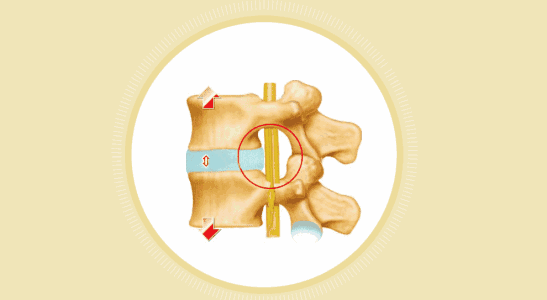

① 臥床休息

由于腰椎間盤突出癥的發(fā)生、發(fā)展與負重和體重有一定的關系。可以通過臥床休息,消除體重對椎間盤的壓力,并在很大程度上解除肌肉收縮和腰椎周圍韌帶的張力對椎間盤所造成的擠壓,使神經根的壓力得以消除。當然,臥床休息可避免較大的彎腰及負重,避免病情加重。